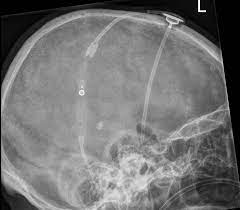

Codman hakim cylindrical valves include a precision fixed pressure valve, a pumping chamber, and an outlet valve with or without a prechamber. The programming method was derived after studying a jammed valve in the. Codman hakim ventil ventil ohne siphonguard ventil mit siphonguard 29 gibt es eine max. Nur das programmierbare codman hakim ventil sollte nach dem mrt durch röntgenkontrolle in seiner einstellung verifiziert werden. Hydrocephalus can be defined as clinically symptomatic dilatation of the internal ventricular system at the expense of brain and blood volume.

Frühere designänderungen an den hydrozephalusventilen, die darauf zielten, die gefürchtete komplikation der überdrainage zu verhindern, erwiesen sich als ungeeignet. Codman hakim shunt valve settings. Codman siphonguard device and valves with the device. In addition to the codman certas plus programmable valve, codman neuro offers the codman ® hakim ® programmable valve, a shunt with 18 settings for when physicians require even finer adjustments. Decq p, barat jl, duplessis e, leguerinel c, gendrault p, keravel y. To spĺňajú prakticky všetky bežné mr prístroje (1,5 t), väčšie pole sa používa len veľmi výnimočne. Codman medos hakim valve can be savely used in idiopathic nph, or due to sah and other etiology. The codman hakim valve is a ventricular shunt valve which can be programmed to open at various csf fluid pressure.

Mit der vorliegenden studie sollte untersucht werden, ob das problem der. Keď chcete mať úplnú istotu spýtajte sa na to pred vyšetrením personálu. In 42.4% of the cases valve pressure adjustment was required at least once (mean number of adjustments 1.2, maximum 23). In 82.8% of cases it was included during the patient's first shunt implantation. Codman® hakim præcisionsventilen er en ventil konstrueret til at åbne ved et enkelt præcist fikseret tryk. Codman hakim precision pressure differential valves. In addition to the codman certas plus programmable valve, codman neuro offers the codman ® hakim ® programmable valve, a shunt with 18 settings for when physicians require even finer adjustments. De fikserede ventiler fås med 10 mmh2o, 40 mmh2o, 70 mmh2o, 100 mmh2o eller 130 mmh2o indstilling. Codman hakim shunt valve settings. 2004 opening to enter secondary path is always open during excessive fl ow, ball seats and closes primary path opening for fl ow to enter inner spiral of secondary path secondary path directs csf through outer spiral to. Gratis versand in 24 stunden bereits ab 20 €. Applying a specific magnetic field to the stepper motor will cause the. Codman medos hakim valve can be savely used in idiopathic nph, or due to sah and other etiology.

Frühere designänderungen an den hydrozephalusventilen, die darauf zielten, die gefürchtete komplikation der überdrainage zu verhindern, erwiesen sich als ungeeignet. Codman medos hakim valve can be savely used in idiopathic nph, or due to sah and other etiology. Arnell k, koskinen lo, malm j, eklund a (2009) evaluation of strata nsc and codman hakim adjustable cerebrospinal fluid shunts and their corresponding antisiphon device. To spĺňajú prakticky všetky bežné mr prístroje (1,5 t), väčšie pole sa používa len veľmi výnimočne. The codman® certas® plus programmable valve is another programmable valve, but with 8 different pressure settings, including a virtual off. Keď chcete mať úplnú istotu spýtajte sa na to pred vyšetrením personálu. In 42.4% of the cases valve pressure adjustment was required at least once (mean number of adjustments 1.2, maximum 23). Das certas ventil is the latest generation of programmable differential pressure certas valves by codman and been declared mri safe up to 3 tesla. A retrospective study of 583 patients. Die druckstufeneinstellung wird in mmh20 angegeben! When reading a skull film with this valve in place, you should give the. Malfunction of a codman hakim programmable valve due to jamming of its programmable component may necessitate shunt revision. The authors report a method for programming jammed codman hakim programmable valves by using a strata ii magnet and additional neodymium magnets.

Diese müssen nach dem mrt nicht auf ihre einstellung kontrolliert werden. Shunt insertion is the mainstay of therapy for communicating hydrocephalus. A retrospective study of 583 patients. Stroke is one of the most devastating diseases, robbing people of their independence and their quality of life. When reading a skull film with this valve in place, you should give the.

Stroke is one of the most devastating diseases, robbing people of their independence and their quality of life. Clinical deterioration was associated with an increase in ventricular size. Codman siphonguard device and valves with the device. The codman hakim programmable valve (codman/johnson & johnson, raynham, massachusetts) permits regulation of the opening pressure between 30 and 200 mm h 2 o. Programovateľný ventil codman hakim môže ísť do mr s magnetickým poľom do 3 t. Codman hakim ventil ventil ohne siphonguard ventil mit siphonguard 29 gibt es eine max. 6 seconds worldwide, a stroke claims a life every 6 seconds 1. Gratis versand in 24 stunden bereits ab 20 €.

Aesculap mininav pressure differential valve. Codman medos hakim valve can be savely used in idiopathic nph, or due to sah and other etiology. Arnell k, koskinen lo, malm j, eklund a (2009) evaluation of strata nsc and codman hakim adjustable cerebrospinal fluid shunts and their corresponding antisiphon device. Shunt insertion is the mainstay of therapy for communicating hydrocephalus. The authors report a method for programming jammed codman hakim programmable valves by using a strata ii magnet and additional neodymium magnets. Die druckstufeneinstellung wird in mmh20 angegeben! De fikserede ventiler fås med 10 mmh2o, 40 mmh2o, 70 mmh2o, 100 mmh2o eller 130 mmh2o indstilling. Gratis versand in 24 stunden bereits ab 20 €. In addition to the codman certas plus programmable valve, codman neuro offers the codman ® hakim ® programmable valve, a shunt with 18 settings for when physicians require even finer adjustments. 5 the valve is often used in series with siphonguard (codman/johnson & johnson), an antisiphoning device intended to prevent overshunting during periods of upright posture (image available. *clinician should confirm valve setting after an mri procedure. Resistance of the codman certas® plus programmable valve to unintended setting changes when exposed to a 3 tesla mri. Frühere designänderungen an den hydrozephalusventilen, die darauf zielten, die gefürchtete komplikation der überdrainage zu verhindern, erwiesen sich als ungeeignet.